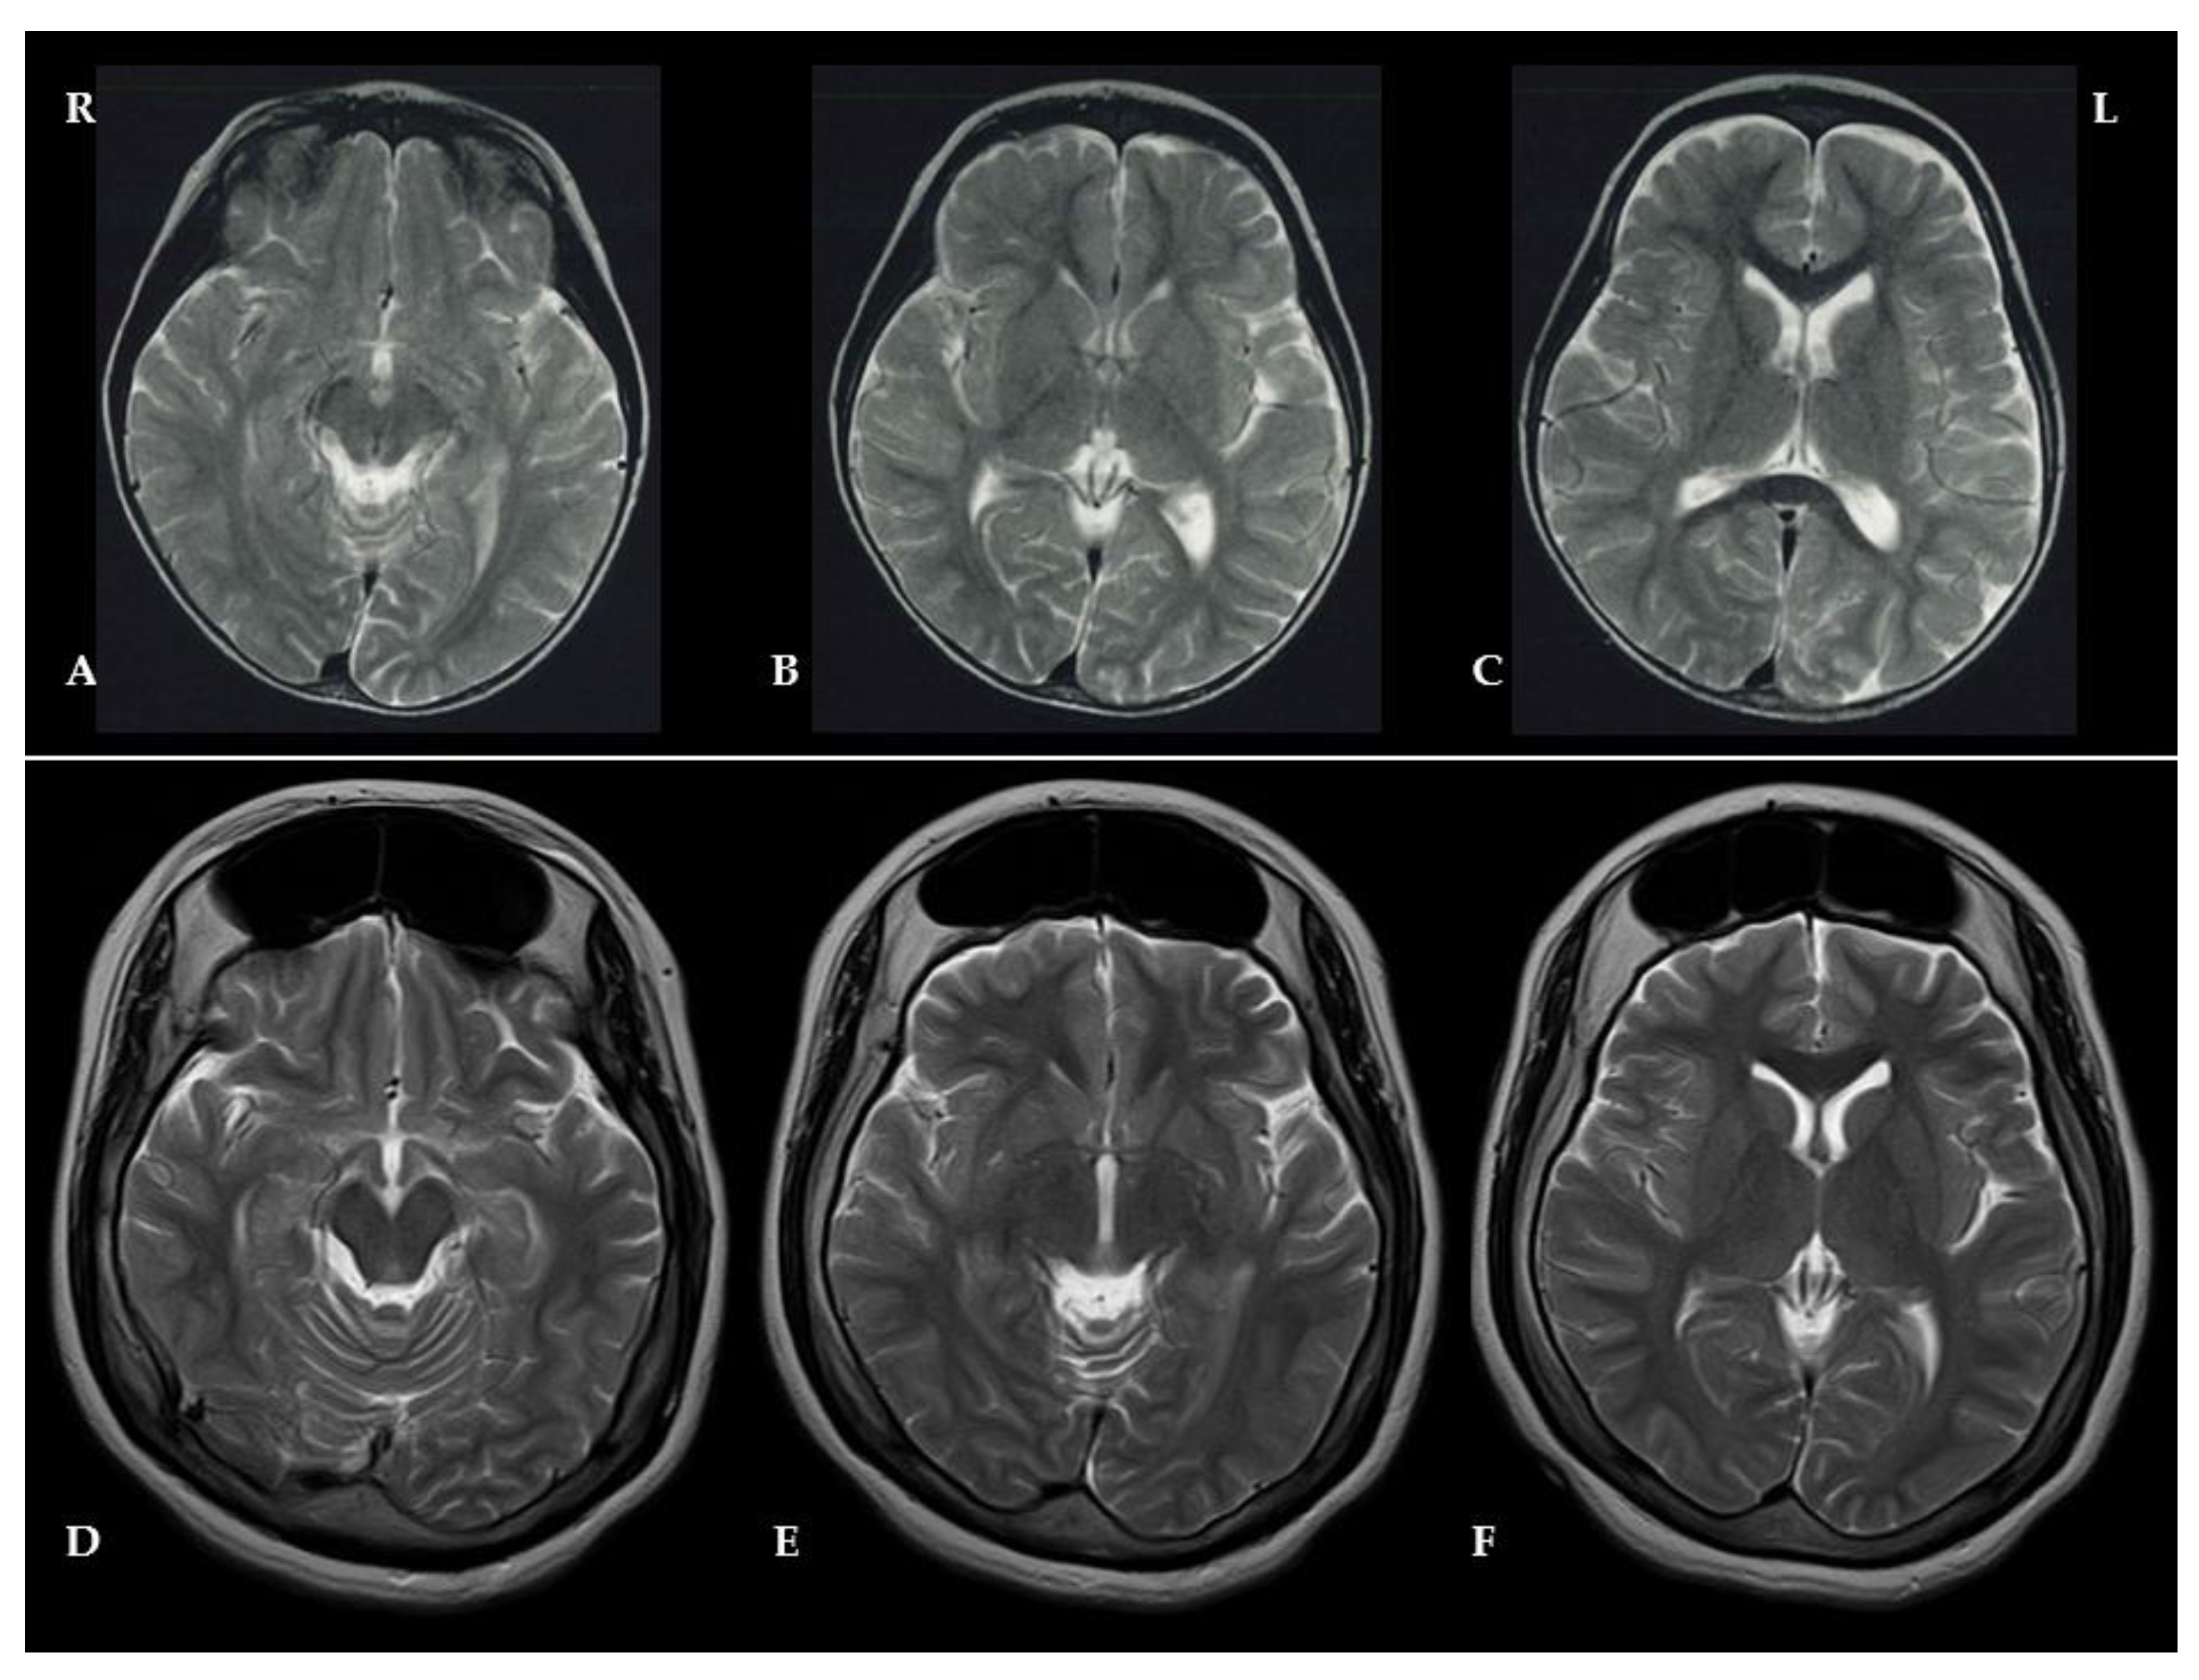

Brain MRI was performed at the age of 2 years with no abnormal findings (Figure 2: A/B/C). Based on these clinical features, Rett syndrome and various other differential diagnoses were suspected, and further genetic analysis was performed.

On physical examination at 16 years of age, her height was 143 cm (-2.6 SDs), her weight was 51.8 kg (+0.1 SDs), and her head circumference measured 57.5 cm (+2.5 SDs), indicative of macrocephaly. This finding was atypical for Rett syndrome, adding another layer of diagnostic complexity. Brain magnetic resonance imaging (MRI) revealed marked thickening of the frontal bone along with bilateral enlargement of the frontal sinuses, findings consistent with hyperostosis frontalis interna (HFI) (Figure 2: D/E/F).

Figure 2. Brain MRI T2-weighted images were obtained at ages 2 (A/B/C) and 16 (D/E/F). At age 2, no significant abnormalities were detected; however, at age 16, there was prominent thickening of the frontal bone, indicative of hyperostosis frontalis interna (HFI). Additionally, bilateral enlargement of the frontal sinuses was observed, suggesting extensive involvement of the anterior cranial vault. The high-resolution T2-weighted imaging facilitated precise visualization of cranial abnormalities, thereby supporting the diagnosis of HFI and underscoring the atypical manifestation of macrocephaly in this case of Rett syndrome.